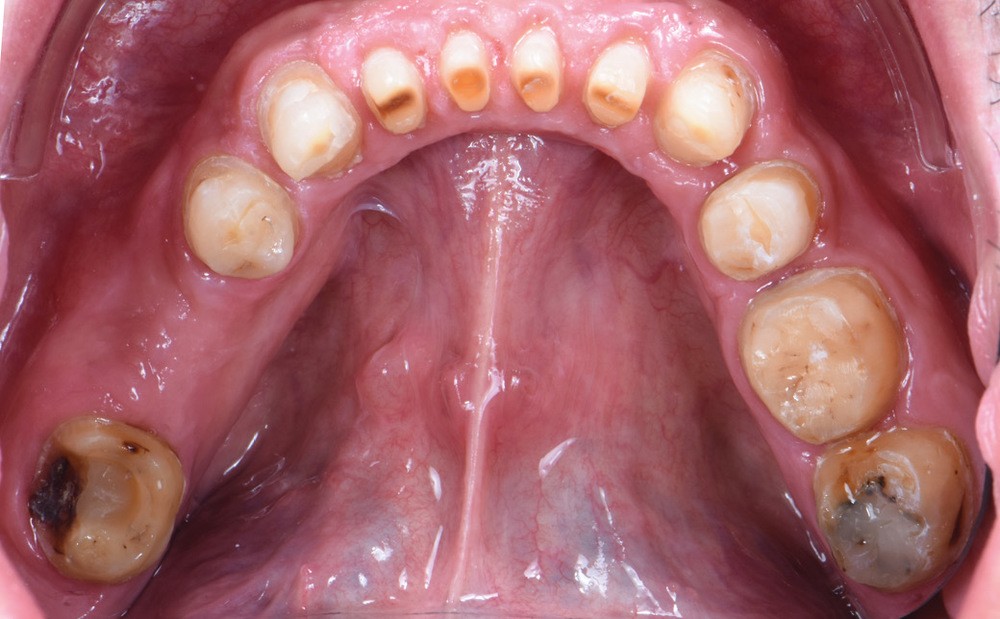

Au vu du contexte para-fonctionnel et de l’étendue de la perte tissulaire, des coiffes périphériques minimalement invasives ont été choisies afin de restaurer l’esthétique et la fonction. Actuellement, aucun consensus n’est fait sur le choix du matériau d’infrastructure à privilégier. Les matériaux hybrides usinables présentent des propriétés mécaniques, physiques et biologiques intéressantes en contexte d’usure sévère (e.g., module d’élasticité, résistance à la propagation de fêlures, facilité de réintervention). Une réhabilitation globale avec remontée de dimension verticale d’occlusion (DVO) par l’intermédiaire de coiffes composites renforcés en nano-céramiques est décrite.